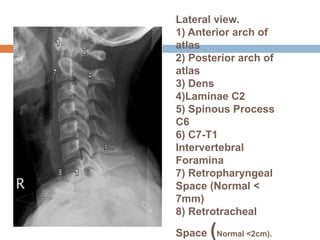

Lateral view.

1) Anterior arch of

atlas

2) Posterior arch of

3) Dens

4)Laminae C2

5) Spinous Process

C6

6) C7-T1

Intervertebral

Foramina

7) Retropharyngeal

Space (Normal <

7mm)

8) Retrotracheal

Space (Normal <2cm).

Lateral view. 1) Anteriorarch of atlas 2) Posterior arch of atlas 3) Dens 4)Laminae C2 5) Spinous Process C6 6) C7-T1 Intervertebral Foramina 7) Retropharyngeal Space (Normal < 7mm) 8) Retrotracheal Space (Normal <2cm).